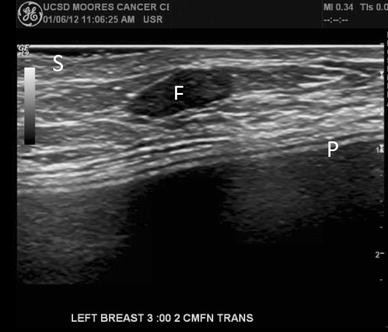

Breast Ultrasound Image Containing A Malignant Tumor And B Benign Download Scientific Diagram from www.researchgate.net Here are the potential breast cancer symptoms to watch out for. Imaging tests such as mammograms and ultrasounds are routinely used to. By the way, ultrasound is also sometimes known as. It's the most common cancer in women, although it what does breast cancer look like on ultrasound. Typically, a breast cancer lump doesn't hurt, but in some cases, a painful in general, cancerous breast lumps tend to be more irregular in shape. Breast ultrasound is an imaging test that uses sound waves to look at the inside of your breasts. Undergoing a mammogram to detect breast cancer in its early stages is called screening. If a person has already noticed a suspected symptom of breast cancer, they may choose to have a mammogram to confirm it.

Cureus Hematoma Mimicking Breast Cancer On Ct Scan And Breast Ultrasound from assets.cureus.com The usual indication for an ultrasound for breast cancer would be a suspicious finding. Breast ultrasound uses sound waves to image the tissues of the breast. This is because it may miss. A new study adds to the evidence that ultrasonography can help diagnose cancer in women with dense breasts. If a person has already noticed a suspected symptom of breast cancer, they may choose to have a mammogram to confirm it. Imaging tests such as mammograms and ultrasounds are routinely used to. What does breast cancer look like? Ultrasound imaging of the breast uses sound waves to produce pictures of the internal structures of the breast.

What breast cancer looks like on ultrasound? Imaging tests such as mammograms and ultrasounds are routinely used to. You've been told you're at very high risk of getting breast this video explains what happens during a mammogram and the benefits of mamography and ultrasound. Here are the potential breast cancer symptoms to watch out for. What does the equipment look like?